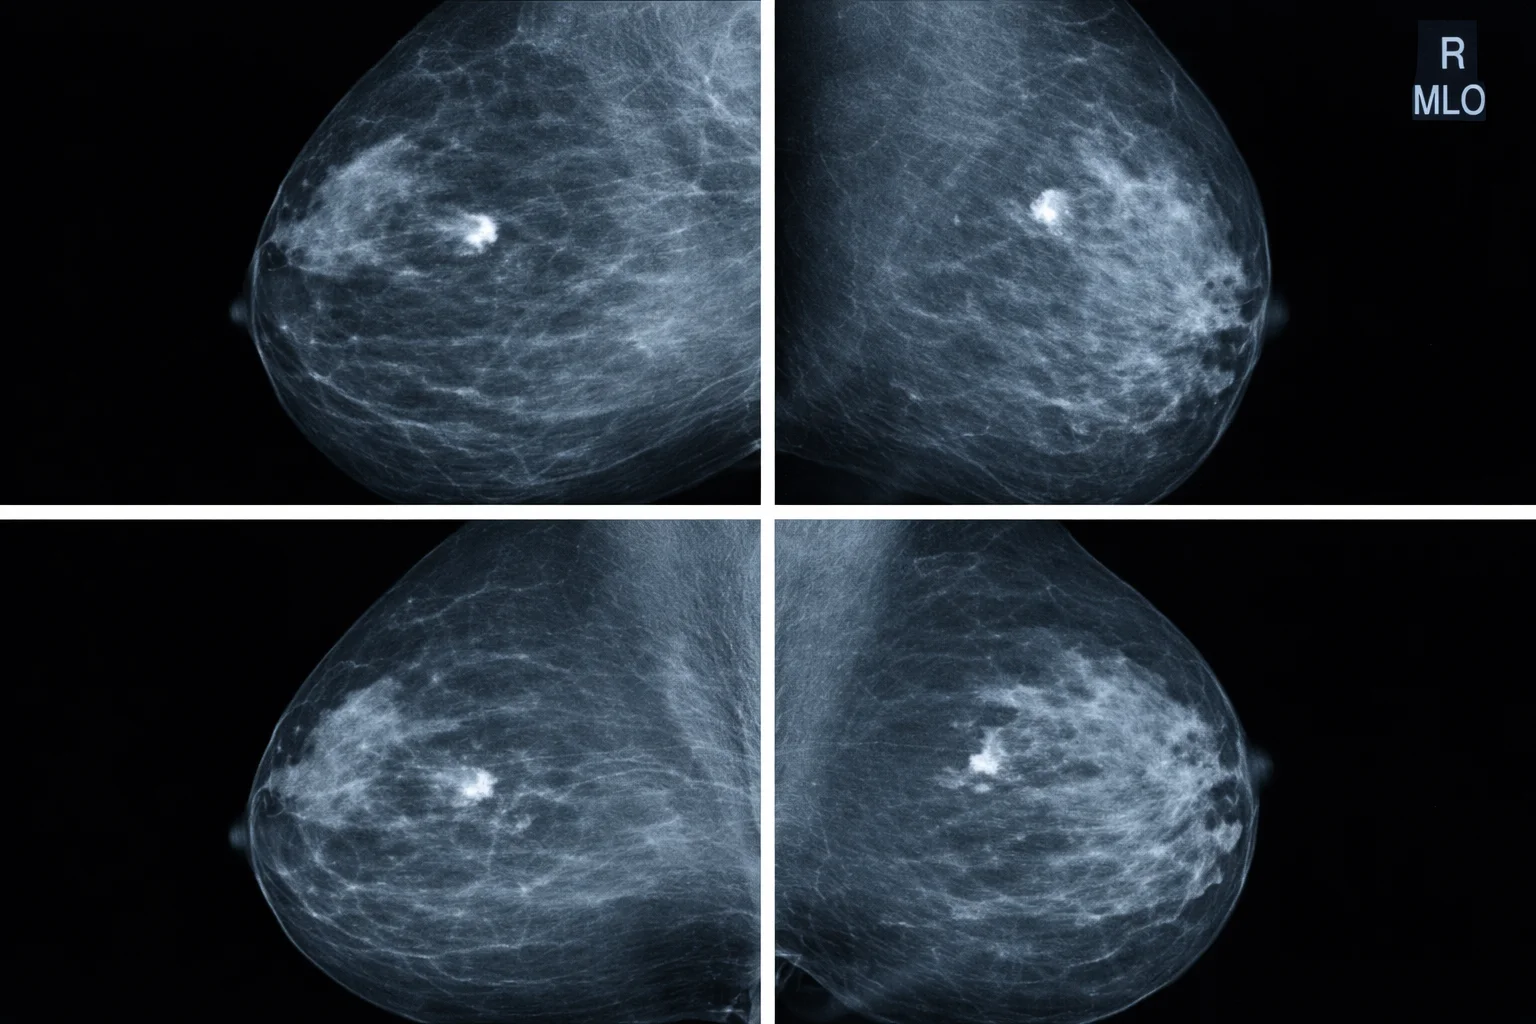

Four mammogram scan images showing different views of breast tissue

At Singapore Women's Clinic, a mammogram typically takes around 15 to 30 minutes and is performed by a female radiographer for your comfort.

2. The radiographer will position your breast on the machine's flat surface. A compression paddle then presses down gently to spread the tissue evenly. Two images are taken, one from above (craniocaudal) and one from the side (mediolateral oblique).